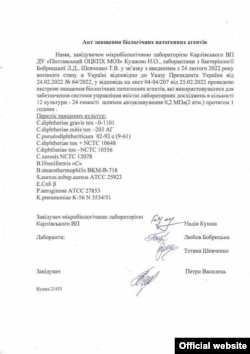

10 марта начальник войск радиационной, химической и биологической защиты (РХБЗ) ВС РФ Игорь Кириллов сообщил, что биолаборатории во Львове работали с возбудителями чумы, сибирской язвы и бруцеллеза, в Харькове и Полтаве – с возбудителями дифтерии, сальмонеллеза и дизентерии.

– Сравните его со списком так называемых особо опасных инфекций. В опубликованном списке препаратов, утилизированных в полтавских и харьковских лабораториях, ничего подобного нет. Давайте разберемся, какие патогены в нем перечислены.

Corynebacterium diphtheriae – это потенциально опасный, но совершенно непригодный для широкого распространения штамм возбудителя дифтерии. Очень трудно заразиться дифтерией, пока вам в горло не вольют полную ложку этой культуры – вот тогда вам будет плохо.

Corynebacterium pseudodiphteriticum – это бактерии, которые являются частью нормальной микрофлоры верхних дыхательных путей и кожи человека. Это уже чисто условный патоген. Он может нанести вред здоровью человека только в условиях иммунного дефицита.

Corynebacterium xerosis – это то, что потенциально у некоторых людей может вызвать воспаление слизистых. Вещь, конечно, довольно неприятная, но лечится специальным кремом.

Baсillus lihenifprmus "С" – это штамм, с которым вы имеете дело постоянно. Он встречается где угодно, даже во вчерашнем борще.

Baсillus stearothermophilis, может, считается условным патогеном, но, опять-таки, этой бациллы нужно проглотить очень много, и даже у человека с иммунодефицитом она не вызовет опасных заболеваний.

Staphilococcus aureus – тоже самая обычная вещь, заразиться которой можно просто из воздуха. Если вы чашку на столе оставите, то каждая сотая колония бактерий, которая там образуется, – это золотистый стафилококк. Да, бывает, что из-за него на горле человека вырастают желтые блямбы, но это не стафилококк виноват, а состояние организма.

Escherichia coli – у нас у всех в кишечнике есть эта кишечная палочка. Если высевать образцы микрофлоры, то у половины людей будет встречаться эта Escherichia coli. Это не очень хорошо, поскольку означает, что мы плохо питаемся и нужно внести изменения в систему питания, но это не означает, что это опасная зараза.

Pseudomonas aeruginosa – это синегнойная палочка, обитающая в воде и почве, она условно патогенна для человека. Klebsiella pneumoniae – тоже условный патоген.

Все, что перечислено в опубликованных документах, – это условные патогены, за исключением Clostridium diphtheriae. Но и этот возбудитель не относится к группе особо опасных патогенов.